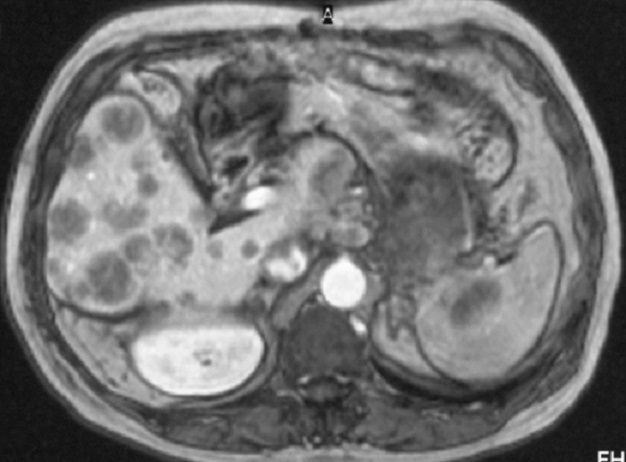

une splenomegalie homogene ou heterogene dans 30% des cas . Image IRM de séquences pondérées en

T2, les lésions lymphomateuses apparaissent avec un signal

plus élevé que le tissu splénique normal

Aspect echographique d'une

lymphome maligne de la rate . La rate est

volumineuse ( slenomegalie ), , composant des

nodules hypoechogene , heterogene de taille variable . On peut en

s'observe image adenopathie hypoechogene

perihilaire , |